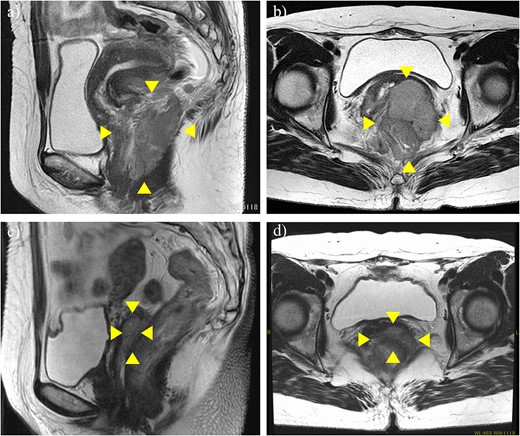

A 51-year-old woman with CC with rectum invasion was referred to our hospital. Vaginal examination revealed a continuous neoplastic lesion extending from the cervix to the vaginal wall, directly invading the rectum. The histopathological diagnosis was squamous cell carcinoma. Her serum squamous cell carcinoma antigen (SCC-Ag) was elevated to 19.2 ng/ml. Magnetic resonance imaging (MRI) and computed tomography (CT) revealed a 91 × 73 mm mass that replaced the cervix and posterior vaginal wall and directly invaded the rectum without hydronephrosis (Fig. 1a and b). Positron emission tomography (PET)-CT revealed no distant metastases. Stage IVA CC was diagnosed according to FIGO 2018.

MRI before neoadjuvant chemotherapy (a, b) and after two cycles of paclitaxel and cisplatin (c, d). Arrowheads show the cervical tumor. The tumor shrank markedly after neoadjuvant chemotherapy.

Although CCRT following colostomy was suggested, the patient refused and strongly preferred surgical cytoreduction. According to a radiotherapist, LC may have been difficult with CCRT because the tumor was too bulky. Therefore, we decided to perform NAC-RS. TP therapy (paclitaxel 175 mg/m2 and cisplatin 50 mg/m2) was initiated as NAC. After two courses of chemotherapy, her serum SCC-Ag was reduced to 1.8 ng/ml. CT and MRI revealed a marked reduction in tumor size (Fig. 1c and d) and the absence of the novel lesion. TPE, including radical hysterectomy bilateral salpingo-oophorectomy, radical cystectomy, Hartmann procedure, pelvic lymphadenectomy, colostomy, and ileal conduit placement, was performed (Fig. 2). The duration of surgery and blood loss were 617 min and 1670 ml, respectively. Blood transfusion was required. Macroscopically, no lesions were observed in the cervix. Pathological examination of the surgical specimen revealed squamous cell carcinoma with left internal iliac node metastasis (ypT4N1M0). The surgical margin was negative for cancer. Recovery was uneventful, and the patient was discharged 21 days postoperatively. Forty-nine days after the surgery, TP therapy was restarted, and another four cycles were administered. Thirty-three months after the completion of adjuvant chemotherapy, the patient was alive without recurrence (Fig. 3).